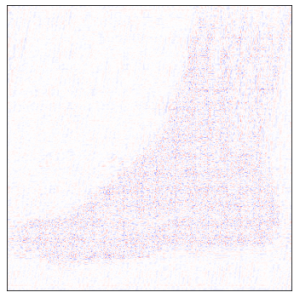

Single-coil results: Table 1 shows that D-GEC outperformed D-VDAMP in all single-coil experiments and outperformed PnP-PDS in all but SSIM at . Figure 5 shows an example of the wavelet coefficients input to D-GEC’s denoiser at the 10th iteration, and their error relative to the true coefficients. Figure 3 shows the evolution of the standard deviation at the input to D-GEC’s denoiser in each subband; there is a good agreement between true and predicted values. Figure 6 suggests that the subband errors are Gaussian. Figure 4 shows image recoveries and error maps for one test image at .